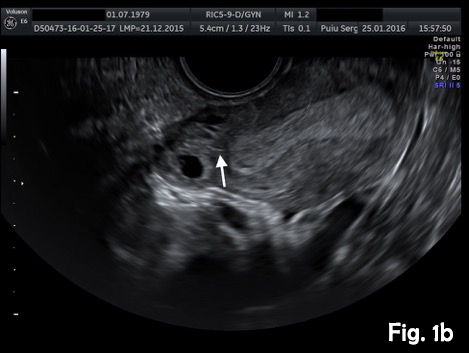

A 37-year-old woman presented for a routine dating scan at 6 weeks amenorrhea. On appointment she was asymptomatic. Transvaginal sonography revealed an empty uterine cavity and a small gestational sac with a yolk sac located eccentrically outside the endometrium, at least 5 mm from the lateral edge of the uterine cavity (Fig. 1a). A thin myometrial layer surrounding the gestational sac and an echogenic line (interstitial line) extending from endometrium to the ectopic sac was clearly seen (Fig.2b). An interstitial pregnancy was presumed. Laparotomy with excision of the interstitial pregnancy was performed. The postoperative period was uncomplicated.

Figure 1b. Transvaginal ultrasound scan (transverse view). Note a thin myometrial layer surrounding the gestational sac and an interstitial line (arrow), extending from endometrium to the ectopic sac.